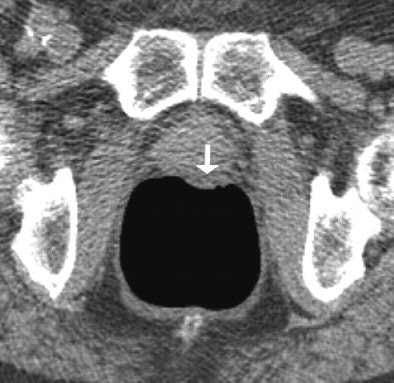

| Above: Supine image of rectum in a 64-year-old woman shows nontagged material 6 mm or greater with small hyperdense spot in dependent part of rectum (arrow). Hyperdense spot probably corresponds to some barium. Below: Prone view of rectum in the same patient shows nontagged fecal material has moved to anterior rectal wall (arrow). Image shows nontagged feces 6 mm or larger in rectum, possibly caused by remnants of bisacodyl suppository. P Lefere, S Gryspeerdt, J Marrannes, M Baekelandt, B Van Holsbeeck, "CT Colonography After Fecal Tagging with a Reduced Cathartic Cleansing and a Reduced Volume of Barium" (AJR 2005, 184: 1836-1842). |

Overall the researchers found residual feces in 413 segments (34.41%), including fecal material smaller than 6 mm in 210 segments (17.5%) and 6 mm or larger in 203 segments (16.92%). In addition, 527 segments contained residual fluid (43.91%), detected as it moved between prone and supine imaging. Nontagged feces 6 mm or greater were present in 49 segments (4.08%) and nontagged fluid in 178 segments (14.83%).

"The false positives were caused in four patients because of diverticulosis with severe luminal narrowing and thickening of the folds," Lefere and colleagues commented. In these cases, a differential diagnosis that included carcinoma was made. Only 4% of segments presented with untagged feces 6 mm or larger, and this result was limited to the presence of one fecal ball in more than two-thirds of these patients.

"The good results of tagging are reflected in the results of polyp detection," Lefere and colleagues wrote. "In fact, there were no false-positive findings caused by nontagged feces. Three false negatives of a total of 68 lesions 6 mm or greater were reported. Only one lesion of 6 mm or greater was overlooked, and it was detected retrospectively. The two other lesions were adjacent to another lesion and were hence misinterpreted as being a bilobulate rather as being two separate lesions."